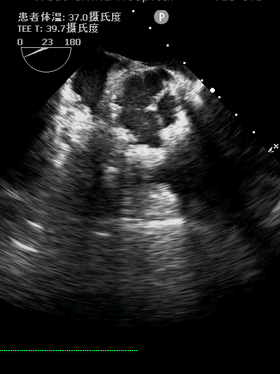

患者入院后完善相关检查,并给予药物支持治疗。术前检查我们发现患者先天性主动脉瓣二叶式畸形 主动脉瓣重度狭窄伴轻中度关闭不全,左室明显增大(LV 60),心功能测值降低(EF% 48%)(图1,2),同时合并升主动脉瘤样扩张(AAO 45)(图3,4)。心脏大血管外科胡佳教授对患者进行了全面的评估,反复与患者沟通手术相关风险和花费后决定为患者实施胸腔镜下肋间小切口免缝合主动脉瓣置换+升主动脉成形术。该方法既可以微创不损伤胸骨,免缝合主动脉瓣术中无需缝合打结,大大缩短体外循环和心脏阻断时间,降低手术风险,又可以在一定程度上降低患者总体费用。完善术前相关准备后手术如期进行。

图5,6